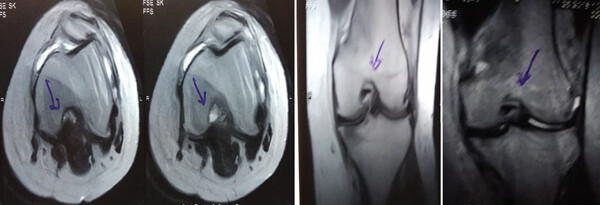

MRI檢查發(fā)現半月板損傷處修復:3D MRI 顯示 2 年時(shí)半月板撕裂難以辨別。

移植滑膜間充質(zhì)干細胞修復前后的3D MRI圖像

結論:滑膜間充質(zhì)干細胞移植后,2年的隨訪(fǎng)中,患者的關(guān)節功能改善,MRI檢查發(fā)現半月板損傷處恢復,沒(méi)有發(fā)生導致研究終止的重大不良事件。可以達到干細胞治療半月板損傷長(cháng)期療效的目標。